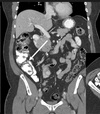

4

Q

1. Descending colon

2. Mesentery

How well did you know this?

1

Not at all

2

3

5

Perfectly